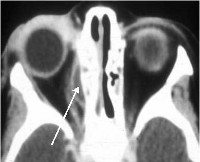

Ультразвуковое исследование глаза и орбиты выявляет изменение размера ретробульбарного пространства, хода экстраокулярных мышц. КТ или МРТ орбит, придаточных пазух носа и головного мозга помогает определить отслойку периоста в зоне поражения. Кроме того, при субпериостальном абсцессе орбиты требуется консультация отоларинголога, челюстно-лицевого хирурга и нейрохирурга. Проводится бактериальный посев гнойного отделяемого с определением чувствительности к антибактериальным препаратам.